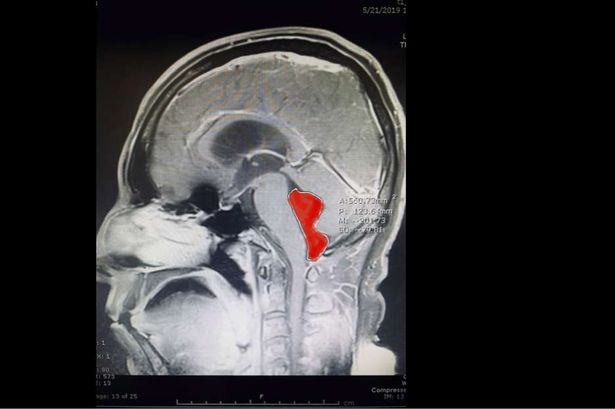

The man had the tapeworm in his brain for a decade (Image: Ascension Seton)

Doctors at the Ascension Seton Medical Centre performed MRI scans of the man’s brain, which revealed that an unusual culprit was responsible for the headaches – a huge tapeworm.

The Taenia solium tapeworm was around five centimetres long, indicating that it had been living in Gerard’s brain for at least a decade.

The tapeworm was found to measure five centimetres long

(Image: Ascension Seton)